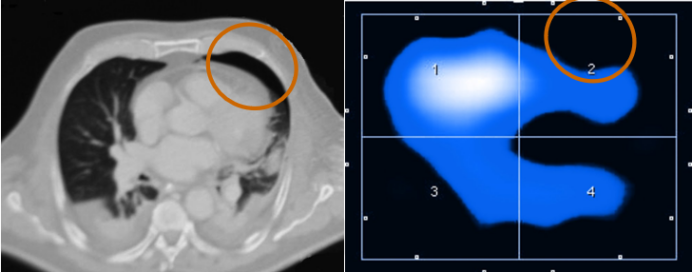

1. EIT评估肺可复张性和指导PEEP滴定

EIT技术能够在自主呼吸试验(SBT)期间,对潮气量的空间分布进行可视化呈现与定量化分析。GI升高或EELV下降(提示肺塌陷发生)时,可作为预测SBT失败的指标。如图3所示,在实施肺复张操作前后,肺部通气状况呈现出显著差异,借助EIT可清晰捕捉并直观展现这种变化,为评估肺复张效果、指导呼吸治疗提供有力依据。

图片

3  肺复张前后肺部通气的分布情况

评估肺的可复张性,可通过对比两个不同时间点潮气图像的阻抗差值实现。将差值以图像形式呈现(差值图像)4,能够精准判别肺内通气阻抗变化的部位,明确是哪些区域的阻抗增加(提示通气改善等可能),又或是哪些区域的阻抗减少(可能存在肺塌陷等情况),从而为判断肺复张效果、分析肺通气功能状态提供直观依据。

4  阻抗差值图像

肺可复张性评估参考流程如下:①设置ROI:采用分层模式,将肺部分为腹侧与背侧区域;②实施肺复张并对比分析:在实施肺复张操作后,对比复张前与复张过程中的肺通气分布状态,核心评估指标为通气分布的均一性是否改善;③判定可复张患者:对于背侧区域(ROI 4)的通气量较复张前出现明显增加的患者,可判定为具备可复张性的患者。图5-7所示为经EIT评估的肺可复张性。

5  有可复张性

6  部分可复张性

7  无可复张性